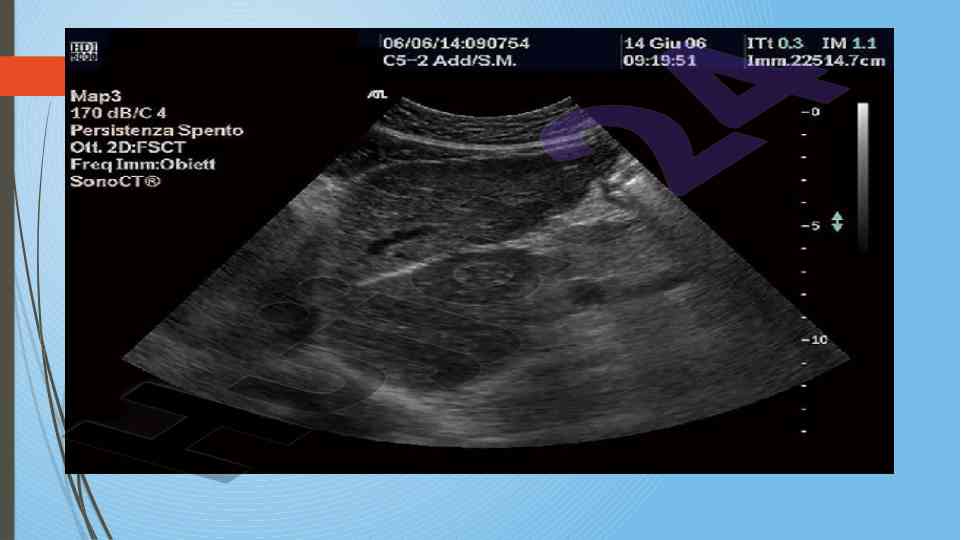

Диссертатсия давомида сурункали гепатитларнинг ультратовуш ташхиси ва этилогиясини ўрганиш. Аутоиммун ва ноалкоголь гепатитларнинг хусусиятлари таҳлил қилинган.